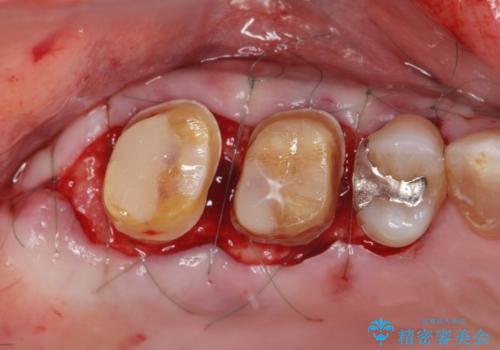

歯周ポケットの除去と再補綴治療

歯周ポケットの除去を歯周外科により行ったのち精度が高く清掃のしやすいセラミック治療による再補綴を行います。

歯を残せるうちに歯周ポケットの除去を行い歯の予後を良くすることができます。